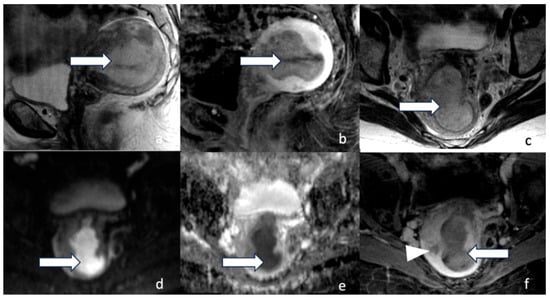

5.3. Magnetic Resonance Imaging (MRI)

5.4. Positron Emission Tomography/Computed Tomography (PET/CT)

5.5. Positron Emission Tomography/Magnetic Resonance Imaging (PET/MRI)